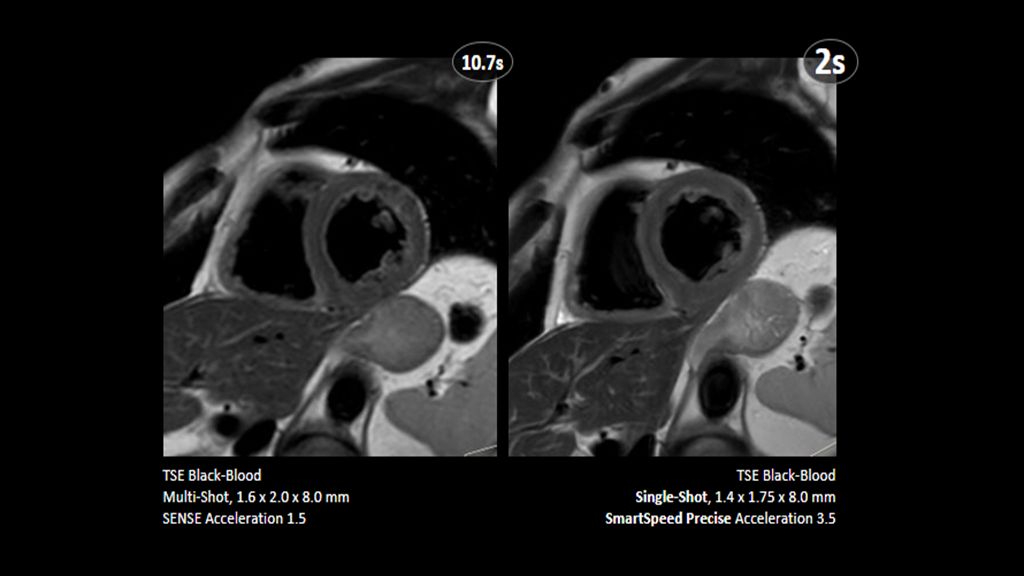

Philips - SmartSpeed Precise - Cardiac NMRF445D MR clinical applications - Philips